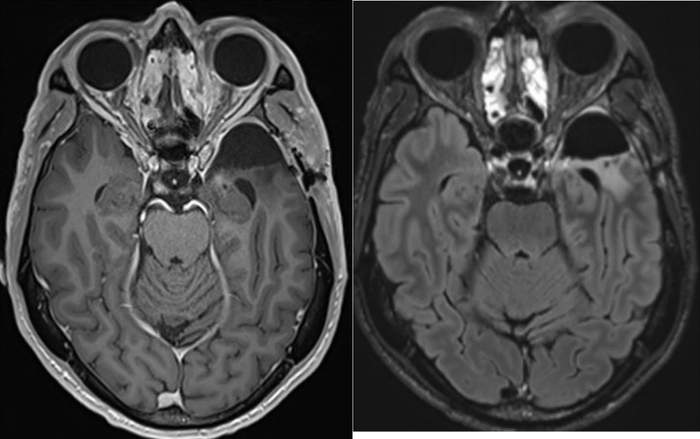

结果如他所料。理查德的肿瘤属WHO Ⅳ级、IDH野生型、MGMT未甲基化,几乎是GBM中预后最差的一类。但也有好消息:经过三联ICI后,组织内多处免疫细胞都有10倍以上增加,提示肿瘤微环境明显改变!

这归功于理查德诊疗方案的第二个不同,即在手术切除病灶前,进行PD-1、LAG-3、CTLA-4等3个免疫检查点阻断治疗。这里用到3种免疫治疗药物,目的是激活免疫系统,增强其杀灭癌细胞的能力。

前述预印版文章重点讨论了三联ICI的安全性、有效性。姚瑜认为,文章是想通过理查德的个案,说明部分GBM患者能耐受三联ICI,以及这有助于丰富肿瘤的免疫微环境、助力治疗。

其次,治疗反应评估是个难题。早期进行免疫治疗会导致炎症反应,或出现独特的影像学改变,看起来像是疾病在进展。实际上,一部分患者仍可以获得长期生存、肿瘤消退等临床获益。据此,RNAO协作组制定“免疫疗法RANO(iRANO)”来确定反应,防止接受免疫治疗的GBM患者过早地被判断为无反应者。